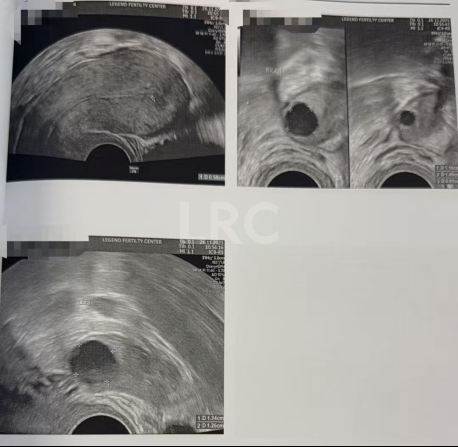

促排第一天

阴超检查:

-右侧 5 颗 (10,9,8,7,6mm)

-左侧 2 颗 (5,2mm)

促排第三天

- 右侧可用卵泡 8 颗(16,12,11,10,9,8,8,8mm)

- 左侧可用卵泡 1 颗 (10mm)